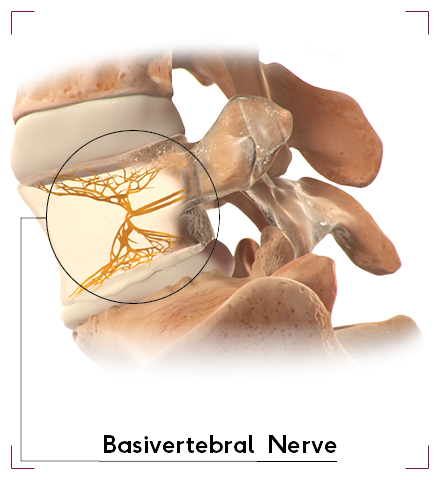

Vertebrogenic low back pain is a term used to describe pain that originates from the vertebral bodies or the intervertebral discs of the spine.

Unlike other forms of back pain that might be muscular or nerve-related, vertebrogenic pain is specifically tied to the bones and cartilage of the spinal column.

The spine is a complex structure made up of vertebrae, which are the bones stacked on top of each other, and discs, which act as cushions between them.

When these components are damaged or degenerate, they can cause pain that is classified as vertebrogenic.